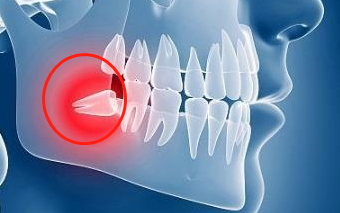

智齒發炎會(hui) 引起麵部腫脹疼痛

但如果智齒發炎臉部腫脹嚴(yan) 重,影響吃飯喝水等,需要注意是否對腹中寶寶有影響,以免出現頜麵部重度感染危害孕婦和胎兒(er) 健康。比如,今日深圳福田8個(ge) 月大的孕婦差點因為(wei) 智齒喪(sang) 命,寶寶出現胎心異常,孕婦頜麵重度感染,醫生為(wei) 其進行手術後才脫離危險,保住了兩(liang) 條命!